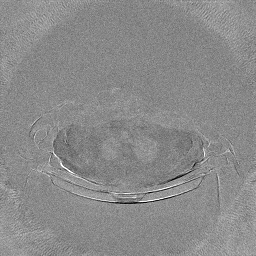

The experimental results on clinical head data are shown in Fig. 4. The reference images were reconstructed using the fast iterative shrinkage-thresholding algorithm (FISTA) with total variation regularization from non-truncated projection data. In the WCE reconstructions (Fig. 4(b)), severe truncation prevents accurate recovery of anatomical structures outside the FOV. Despite being trained solely on simulated data with a domain gap, all deep learning models can restore a substantial portion of the missing anatomy. Among them, the diffusion-based methods recover soft-tissue boundaries more faithfully than the conventional deep learning approach FBPConvNet, highlighting their stronger image generation capability. However, cDDPM reconstructions exhibit more noticeable noise than those from other methods, consistent with the simulated data results. The patchDiffusion model introduces artifacts within the FOV, likely due to its patch-wise processing strategy. While I2SB shares the same limitations as other diffusion models in perfectly restoring soft-tissue detail, it produces fewer residual noise patterns and fewer artifacts within the FOV boundaries. Overall, Fig. 4 demonstrates the strong efficacy of I2SB in reconstructing real CBCT data.